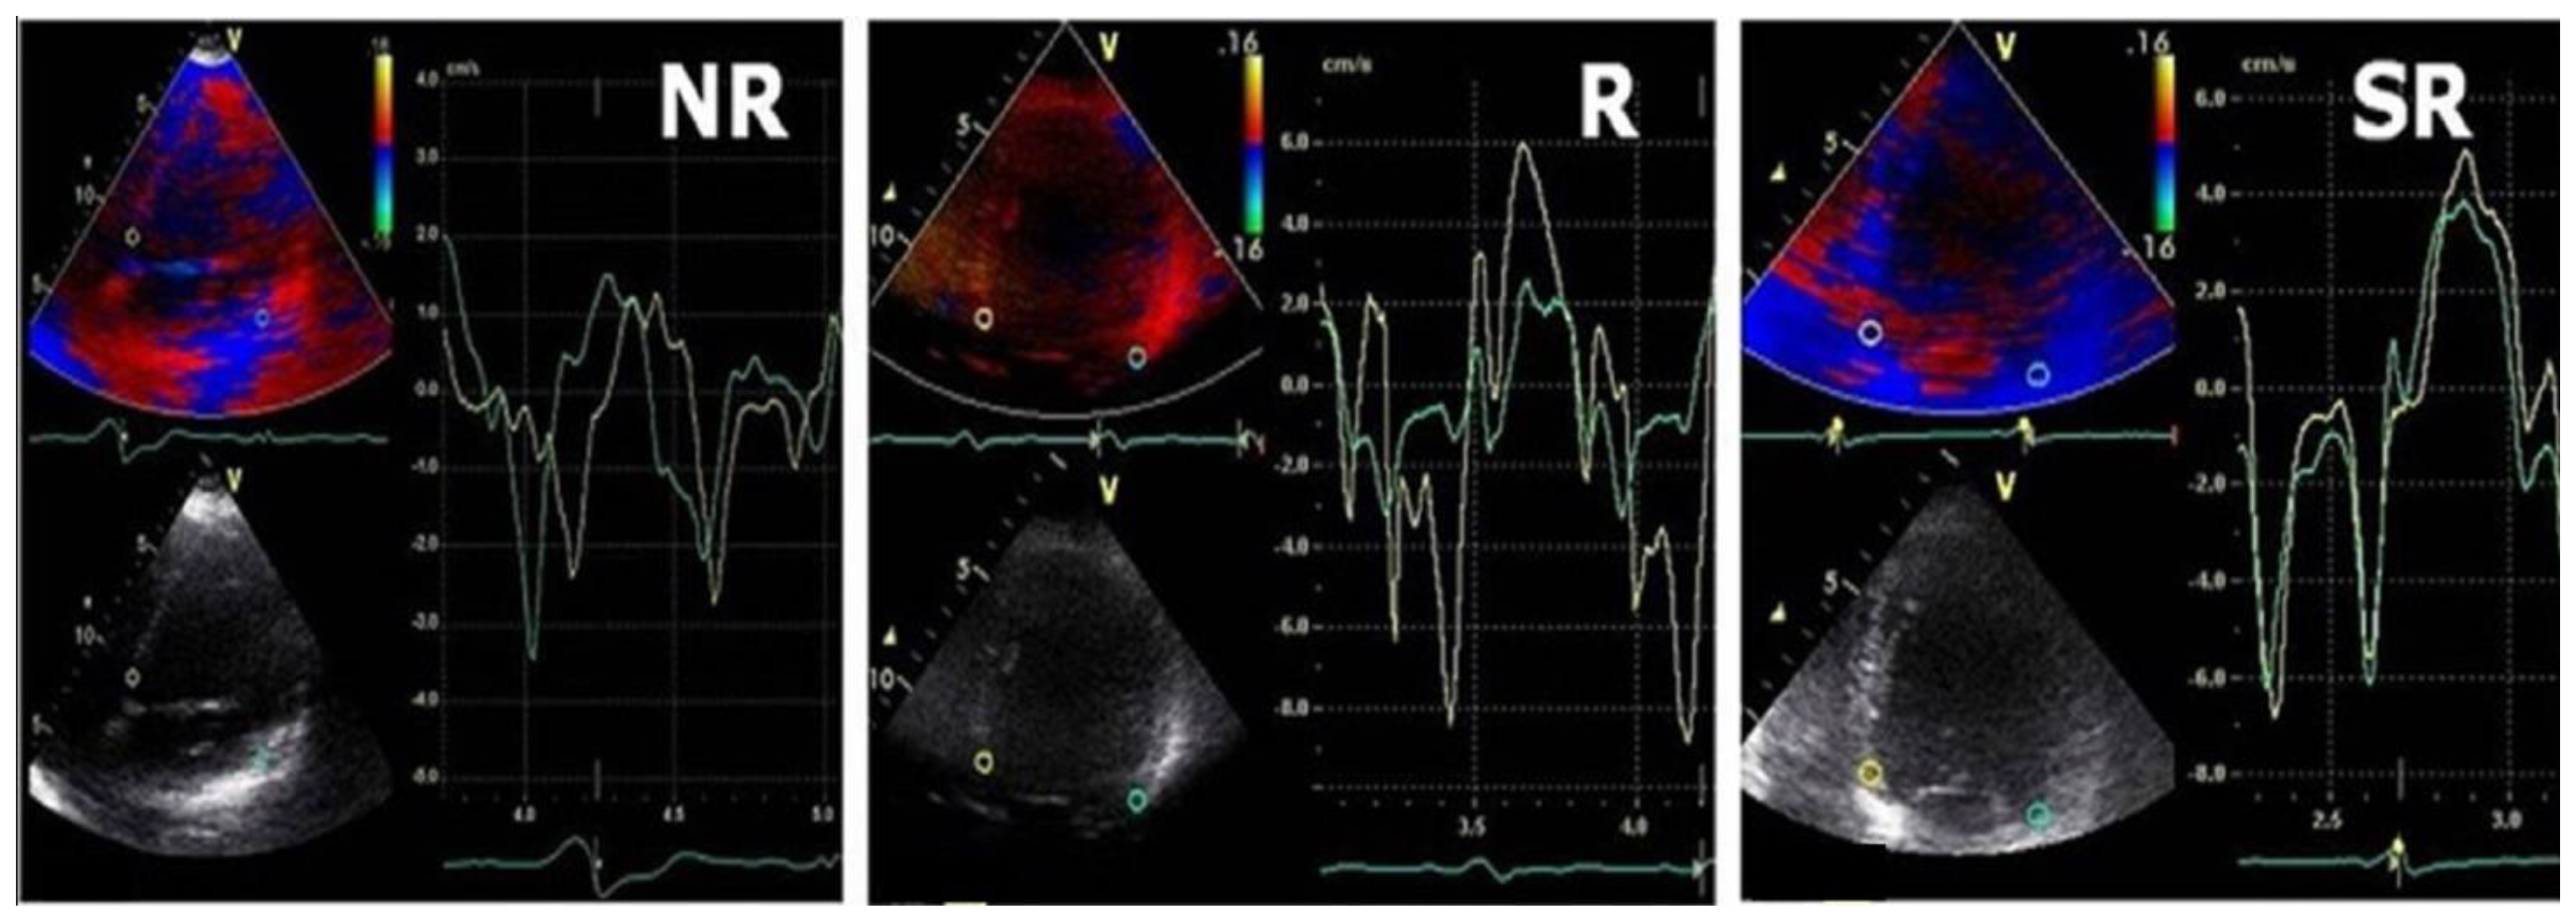

Among the baseline echocardiographic parameters in responders when compared with non-responders, DD profile improved in 65% of patients, reaching a significant statistical importance in E/E′ ratio both in super-responders and in responders. Both E″T and A″T were significantly decreased in responders when compared with baseline (76 ± 13 vs. 51 ± 11 and 26 ± 8 vs. 7 ± 5), and the non-responders group was associated with larger baseline E″T and A″T and no statistically significant difference was noted in these patients after CRT. (Figure 2 and Figure 3).

Figure 2.

Typical TDI patterns in LV fusion pacing in SR/R/NR groups; green line = lateral velocity curve, yellow line = septal velocity curve.